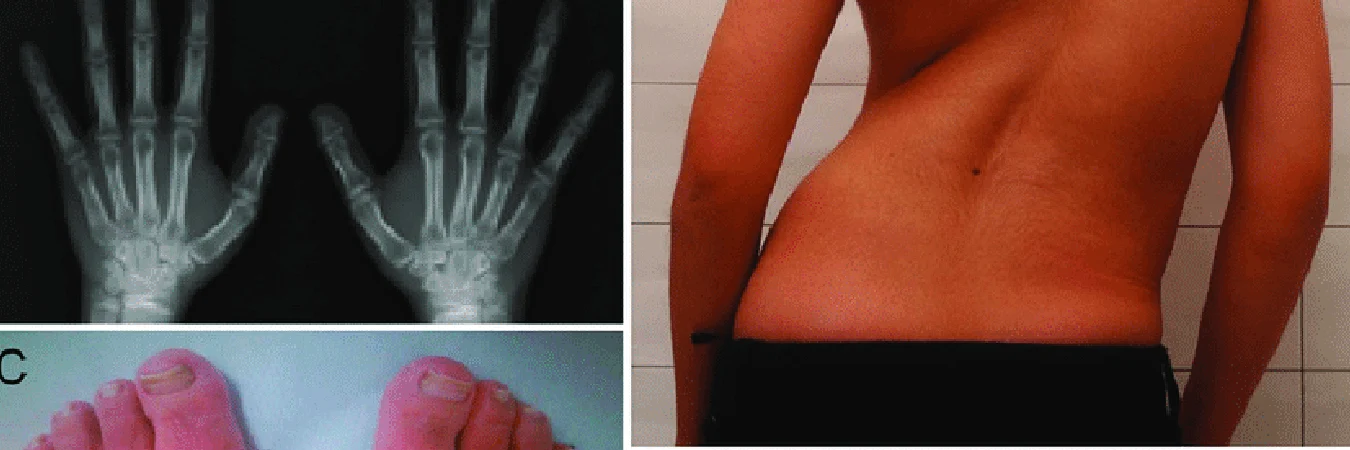

When a patient seeks my diagnosis, I often initiate the process by ordering X-rays to rule out mechanical issues like arthritis or bone spurs. A significant part of the evaluation involves an in-depth discussion with the patient, coupled with physical tests to assess the integrity of their radial nerve. During this dialogue, I inquire about their lifestyle, occupation, hobbies, and any repetitive motions they routinely perform.